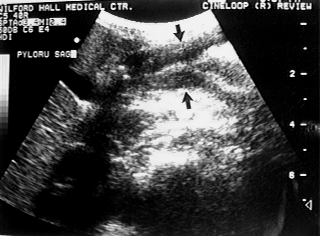

An UGI series in a 3 year old male with solid food intolerance and vomiting demonstrates an elongated and narrowed antropyloric region, also seen on ultrasound (arrows). Marked antral wall thickening was confirmed by upper endoscopy.